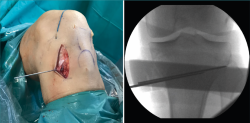

Figura 11. Escopia intraoperatoria de una osteotomía de deflexión. A: colocación de aguja guía paralela a la pendiente tibial; B: extracción de la cuña anterior una vez realizada la osteotomía preservando un puente óseo posterior; C: fijación de la osteotomía de cierre anterior con 2 placas de epifisiodesis y de la tuberosidad tibial con 2 tornillos corticales.

Se utiliza una incisión longitudinal anterior centrada o levemente medial a la tuberosidad tibial anterior (TTA). Primero se realiza una osteotomía de la TTA con un bloque óseo de 6 cm que se rebate hacia lateral permitiendo el acceso libre a la parte proximal de la tibia. La osteotomía de deflexión se realiza de acuerdo con el cálculo preoperatorio. Bajo el control fluoroscópico, se insertan 1 o 2 agujas guía desde la cortical anterior a la posterior de la tibia para marcar el sitio de la osteotomía, comenzando aproximadamente 3-4 cm distal a la interlínea articular, en dirección de la inserción del ligamento cruzado posterior (LCP) (Figura 11A). Mantener un puente óseo posterior intacto es fundamental para proteger las estructuras poplíteas y limitar el riesgo de desplazamiento secundario o pseudoartrosis (Figura 11B). El objetivo es obtener una PTP de entre 0 y 10° según la gravedad de la deformidad y la inestabilidad de la rodilla. La osteotomía de cierre anterior se fija con 2 grapas o 2 placas de epifisiodesis de tipo 8 colocadas en la parte medial y lateral con respecto a la TTA. La tuberosidad se vuelve a reposicionar desplazándola distalmente con una cantidad igual al grosor del fragmento óseo eliminado, para evitar el cambio postoperatorio de la altura patelar, y se fija con 2 tornillos corticales anteroposteriores: uno superior y otro inferior a la osteotomía (Figura 11C).

El túnel tibial para la revisión de la RLCA se perfora de forma estándar, evitando un posible conflicto con el material de osteosíntesis de la osteotomía.